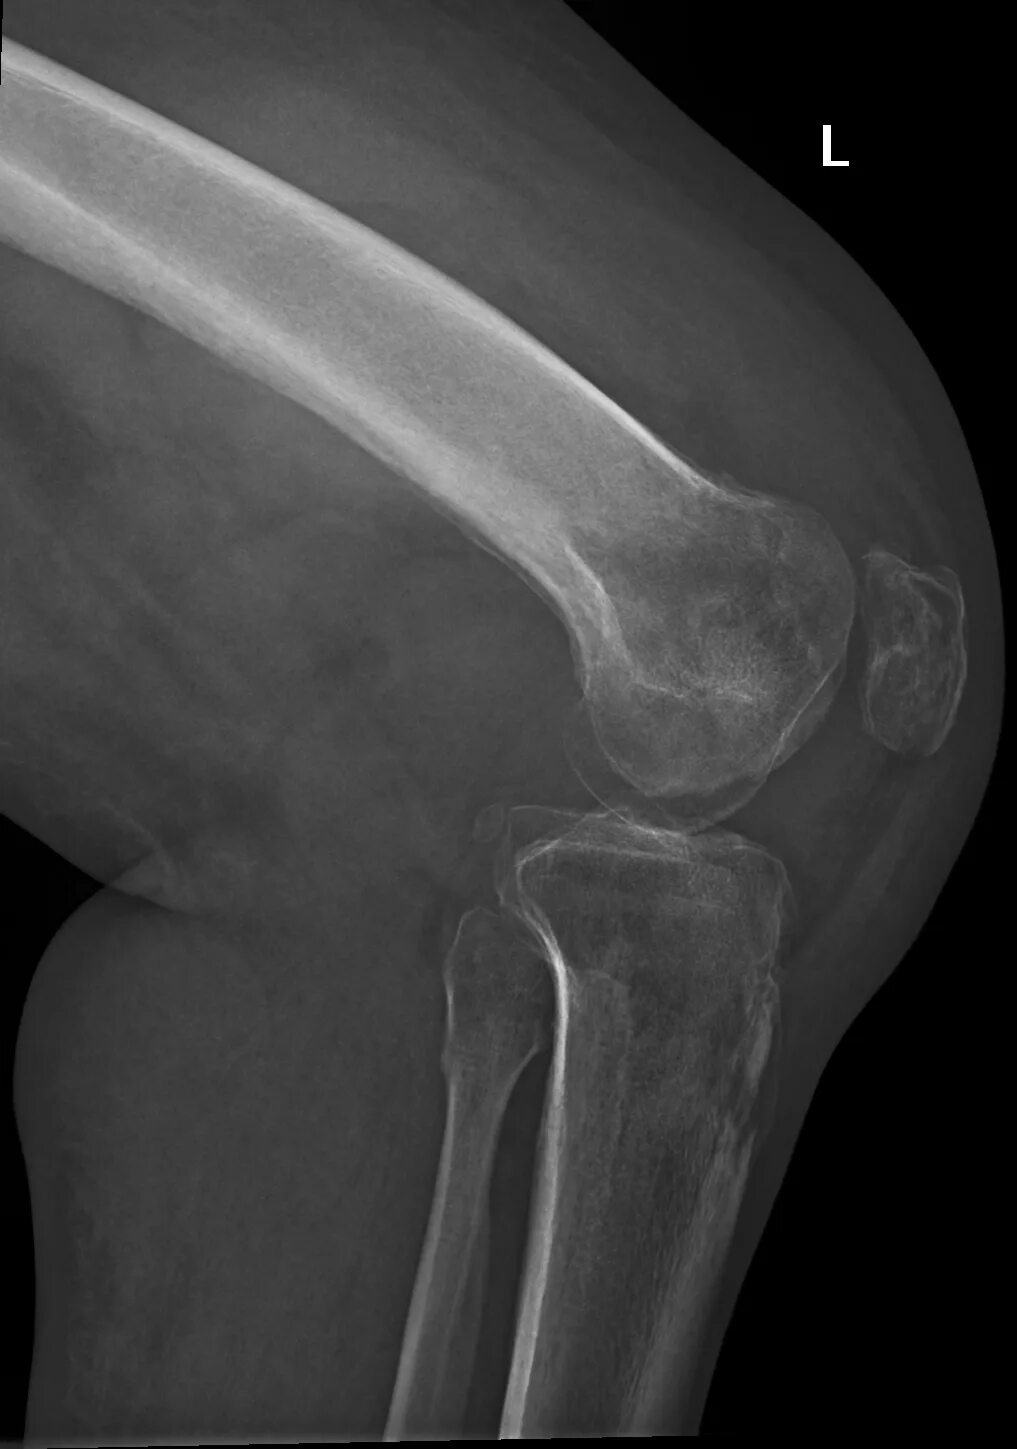

Туберкулез суставов симптомы